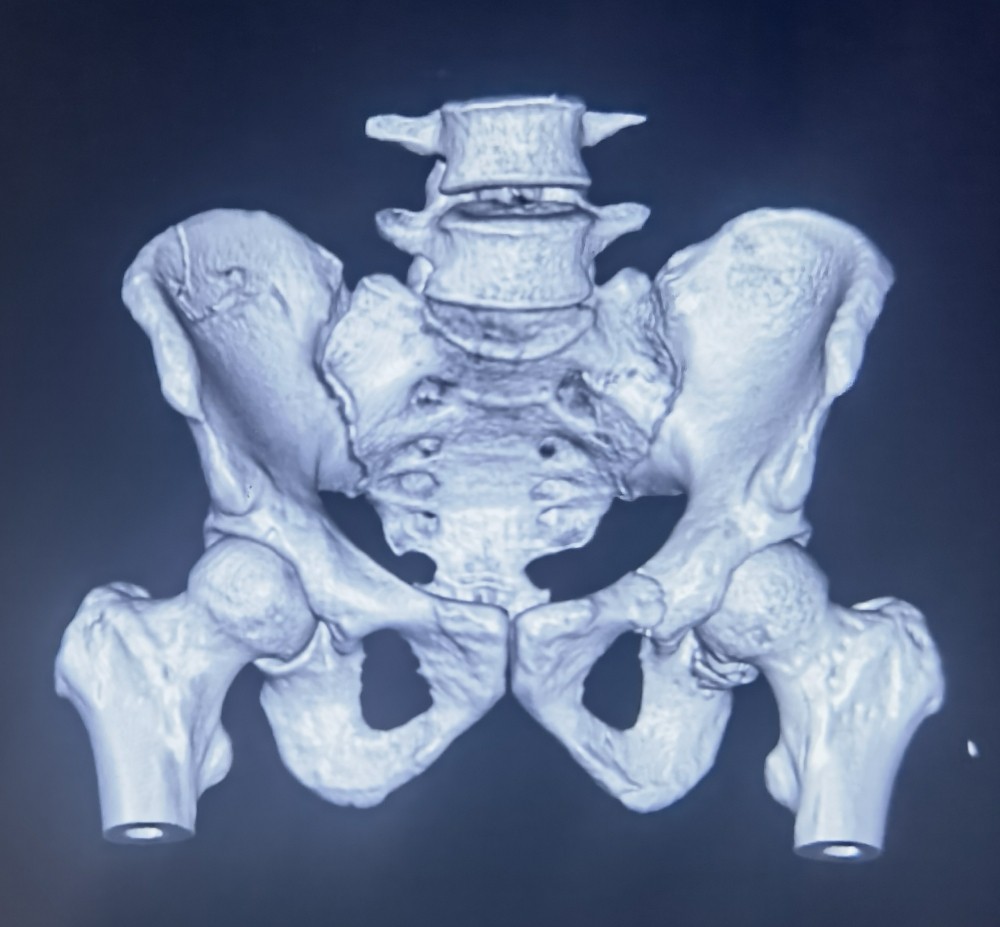

骨盆骨折被称为创伤骨科的“皇冠”,骨盆外观不规则,螺钉安全通道极为狭窄,手术难度高。术中经过C臂环扫后得到患者骨盆三维图像信息,经计算机模拟设计出最佳置钉方案,由机械臂精准引导植入各螺钉,术中出血仅15ml,切口长度不足1cm。真正做到了精准、微创治疗。